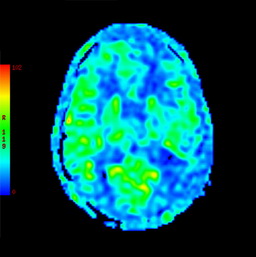

之后,医生为殷阿姨完善了其他检查,颅脑海马+MRA显示:1.双侧基底节区多发腔梗灶;2.脑白质变性;3.幕上(包括双侧海马)弥漫性脑萎缩,以左侧颞叶为著; 4.脑MRA检查提示脑动脉粥样硬化(图一)。颅脑ASL提示:全脑3D-ASL序列检查提示左侧额颞顶枕叶及右侧颞顶枕叶多发稍低灌注区,以左侧大脑半球为主(图二)。

头颅ASL图二